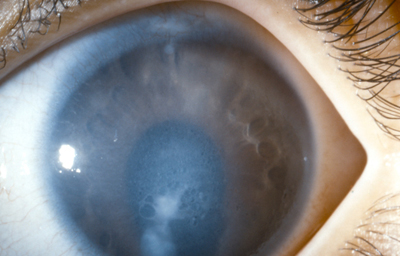

Al examen: OD Edema corneal con Queratopatía bullosa, “Atro a del Iris”, Opacidad subcapsular anterior;. Tensión ocular digital media. Secuelas tóxicas de picadura (Foto No12)

Foto 12 - Foto con edema total de la córnea, despigmentación del Iris y opacidad subcapsular anterior

En el OI: Antecedente de trauma craneoencefálico 20 años antes, con la rama de un arbol. Córnea con nubéculas múltiples puntiformes; Catarata subcapsular anterior y posterior en roseta. Tensión ocular 12, Recesión angular, polo posterior bien.

Se programa para Queratoplastia penetrante OD y Aspiración de catarata en el Ojo Izquierdo.- NO REGRESÓ